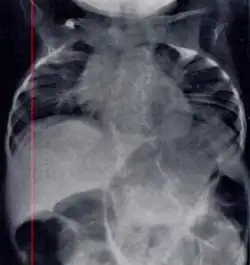

Radiograph depicting typical skeletal features of Jarcho-Levin syndrome, subtype spondylothoracic dysplasia. Note fanlike configuration of the ribs, with extensive posterior fusion, along with multiple vertebral segmentation defects. | |

Spondylothoracic dysplasia, or STD, has been repeatedly described as an autosomal recessively inherited condition that results in a characteristic fan-like configuration of the ribs with minimal intrinsic rib anomalies. Infants born with this condition typically died early in life due to recurrent respiratory infections and pneumonia due to their restricted thorax.[3][4][5] Recently, a report[6] has documented that actual mortality associated with STD is only about 50%, with many survivors leading healthy, independent lives.